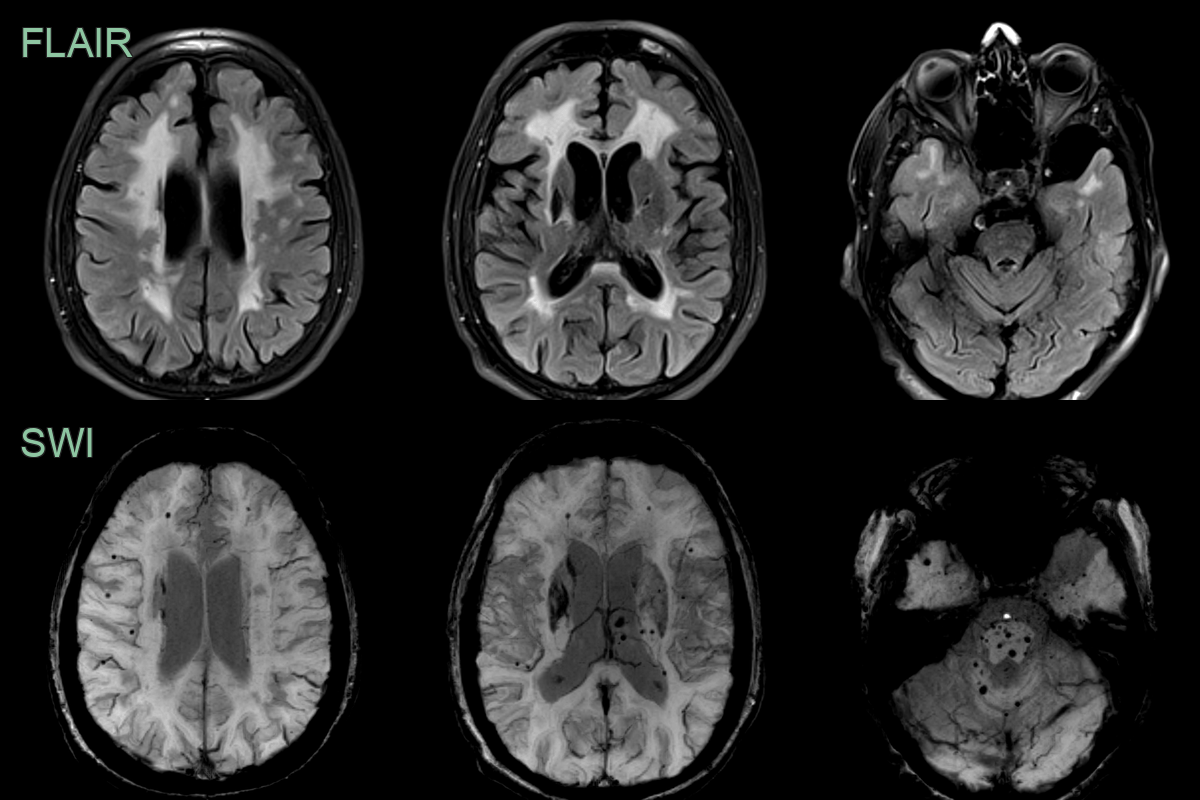

• 50-year-old patient with no cardiovascular risk factors had recurrent strokes.

• MRI showed a severe burden of small vessel disease, multiple lacunar infarcts and mixed distribution microhemorrhages.